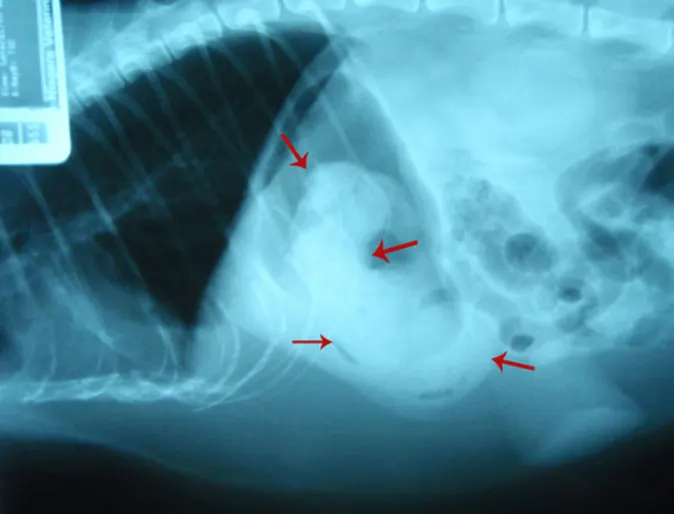

The Importance of Spaying

Scimpi is an elderly female Shih Tzu who came in very lethargic and not eating. She wasn’t spayed and the owner noticed some discharge from her vulva area for a few weeks. On examination her abdomen appeared distended on palpation and she had a mild fever.